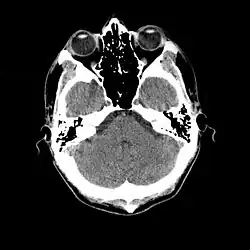

More recently, computed tomography has played a large role in reconstructing endocasts. The procedure is non-invasive and has the advantage of being able to analyze a fossil in record time with little risk of damaging the fossil under review. CT imaging is achieved through the application of x-rays to produce tomographs, or sectional density images, which are similar to the images produced during MRI scans.[8] CT scans use slices approximately 1 mm thick to reconstruct a virtual model of the specimen.[9] This method is especially useful when a fossil cranium is occupied by a natural endocast that cannot be removed without destroying the skeletal portions of the fossil. Because the cranium and its contents are of different densities, the endocranial cavity and its unique traits can be reconstructed virtually.[8]

Radiographic technique such as computed tomographic imaging, or CT scans, coupled with computer programming have been used to analyze brain endocasts from as early as 1906.[10] Recent development of advanced computer graphics technology have allowed scientists to more accurately analyze of brain endocasts. M. Vannier and G. Conroy of Washington University School of Medicine have developed a system that images and analyzes surface morphologies in 3D. Scientists are able to encode surface landmarks that allows them to analyze sulcal length, cortical asymmetries and volume.[11] Radiologist, paleoanthropologists, computer scientists in both the United States and Europe have collaborated to study such fossils using virtual techniques.[10]

Statistical analysis of brain endocasts gives information on the increases in overall brain volume ("endocranial volume"). Because endocasts are not exact replicas, or exact casts, of a once-living brain, computer algorithms and CT scans are needed to calculate endocranial volume. The calculated endocranial volume includes the meninges, cerebrospinal fluid, and cranial nerves. Therefore, these volumes end up larger than the once-living brain.[4] This information is useful for calculating relative brain size, RBS, and encephalization quotient, EQ. The corresponding body weight of the subject must also be known to calculated RBS. RBS is calculated by dividing the weight of the brain by body weight. EQ can be determined several different ways depending on the data set used. For example, Holloway and Post calculate EQ by the following equation:

Many paleoneurobiologists measure cranial capacity via the submersion method, in which displacement of water in a beaker is taken as the volume of the endocast. Scientists who believe that this method is not accurate enough will use a similar procedure in which a beaker with a spout is filled until it is full. The water displaced by the endocast is then weighed to determine the endocast volume. Although both of these techniques are significantly more precise than previous methods, scientists are optimistic that more advanced techniques such as computed tomography will provide greater accuracy of volume measurements.[7]